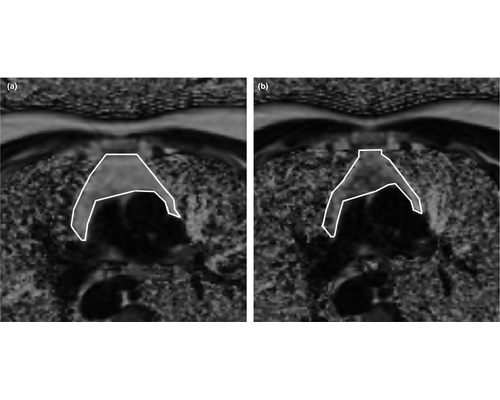

9.我國自主研發(fā)臨床全數(shù)字PET/CT裝備獲準(zhǔn)進(jìn)入市場

華中科技大學(xué)謝慶國教授團(tuán)隊(duì)發(fā)明的全數(shù)字PET/CT,已于2019年5月31日通過國家藥品監(jiān)督管理局注冊審批,獲得市場準(zhǔn)入和對外銷售資質(zhì)。這意味著國產(chǎn)全數(shù)字PET打破國際技術(shù)壟斷,我國高端醫(yī)療儀器開發(fā)取得重大突破。

PET是正電子發(fā)射斷層成像的簡稱,是繼超聲、CT和核磁共振之后當(dāng)今的尖端醫(yī)學(xué)影像技術(shù),在惡性腫瘤、神經(jīng)系統(tǒng)疾病、心血管疾病等重大疾病早期診斷、療效評估、病理研究等方面,具有極大應(yīng)用價值。